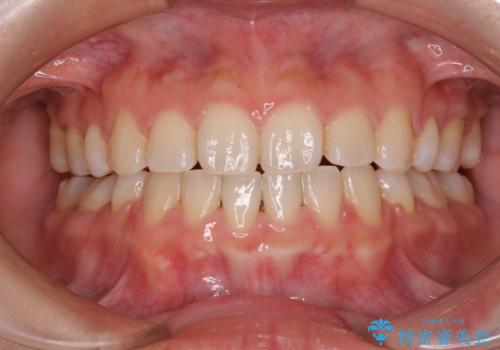

前歯の隙間を閉じたい 短期間でのワイヤー矯正

- 上の前歯の隙間を気にして来院された患者様です。

インビザラインの自己管理は自信がないとのことで、ワイヤー矯正により隙間を閉じていくこととしました。

下の前歯が上の前歯を突き上げるように咬合するため、咬み合わせの位置を改善しながら隙間を閉じていきました。

元々の歯並びが悪くなかったため、9ヶ月で綺麗に仕上がりました。

すきっ歯は後戻りを起こしやすいため、上下ともに歯の裏側を細いワイヤーで固定した上で、リテーナーのマウスピースを装着していただいています。